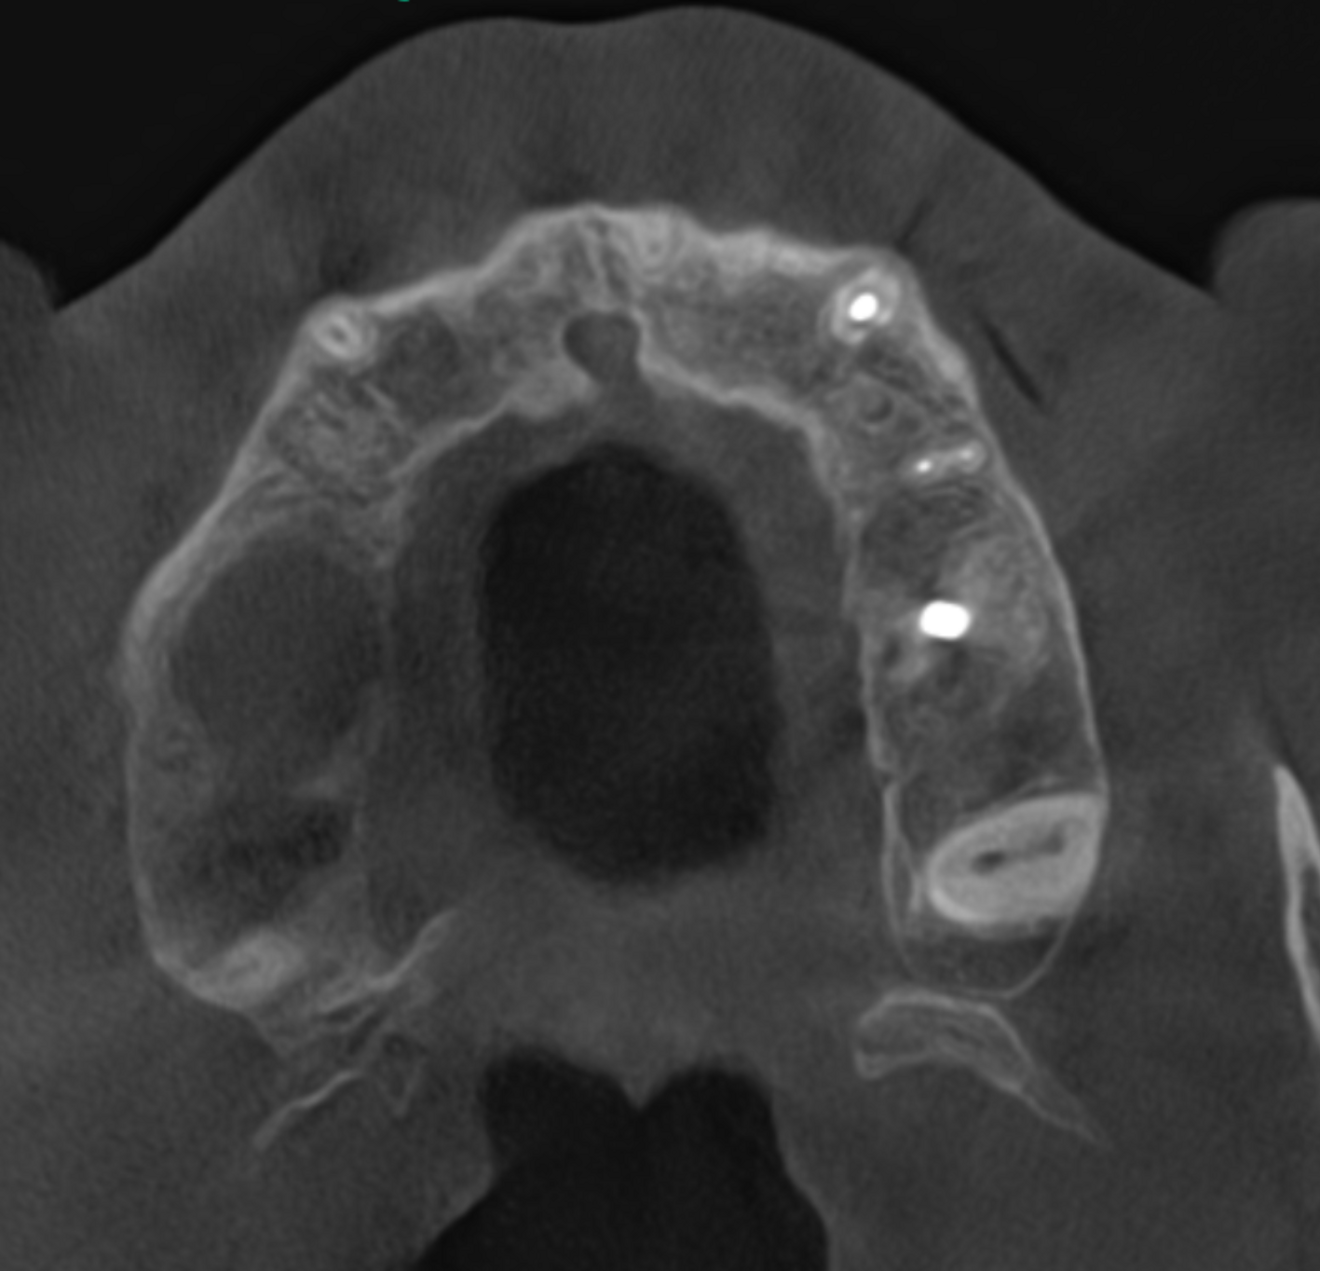

Fig. 5a: Large-volume CBCT scan. Transversal cross-section of the maxilla showing bone loss around the roots of tooth #17 and cortical wall damage.

The 61-year-old male patient wanted to have his missing maxillary right teeth replaced with implants. After examination by an implantologist, he was referred to our dental office for further dental treatment because of the findings of a small-volume CBCT scan taken: advanced inflammation and bone loss were visible in the periodontal tissue of the maxillary right second molar and severe maxillary sinusitis was observed (Figs. 1a & b).

The extent of the inflammation was shocking (Figs. 2a & b). Not only the maxillary sinus (Fig. 3) but the ethmoid and sphenoid sinuses too were involved, and the inflammation had spread towards the right cavernous sinus as well (Fig. 4). At this point, extraction may have been the first choice for most dental clinicians, but we had to keep in mind that invasive treatment may have increased the risk of cavernous sinus thrombosis, a potentially avoidable possibility. There are very few circumstances under which a dental procedure can cause very severe or even lethal consequences, but this case approached such a situation.